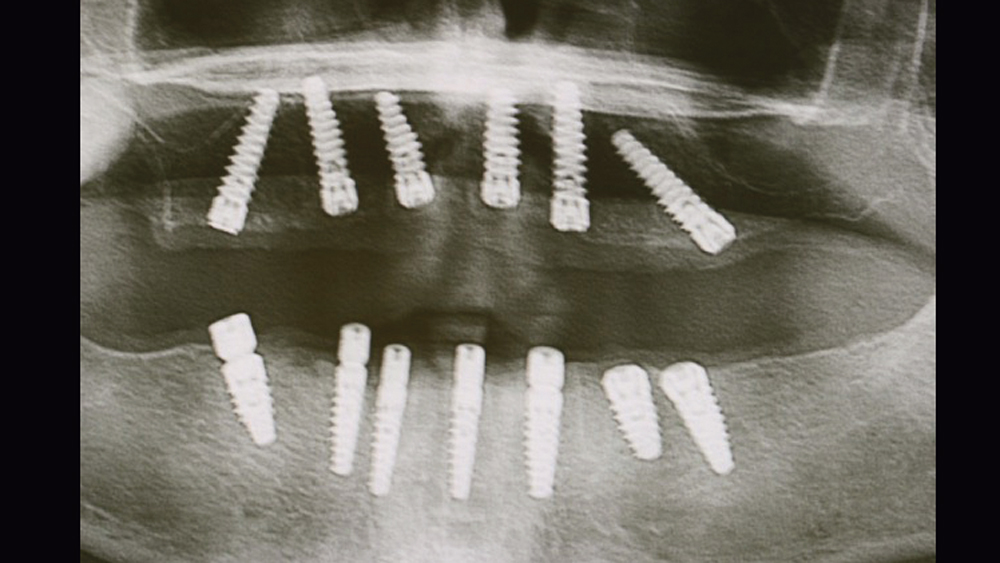

To establish the foundation needed for a screw-retained restoration and avoid fracturing the facial plate, clinicians must position the immediately placed implant against the lingual or palatal wall of the extraction socket. This is one of the reasons I designed the Hahn™ Tapered Implant (Glidewell Direct; Irvine, Calif.) with deep, sharp threads, which enable precise directional control during insertion and prevent the implant from “walking” toward the facial plate as it is threaded into place. This thread design also leads to high primary stability in all bone types, which is essential when performing the extraction with immediate implant placement procedure.1,2

Once osseointegration is complete, the BruxZir® Full-Arch Implant Prosthesis is the ideal choice for the restoration, as its monolithic construction prevents chips, stains, breakage, and dislodged or worn-down prosthetic teeth.3,4 This treatment option has helped elevate the quality of care I’m able to provide for my edentulous patients, who no longer return to my office with a broken acrylic appliance in hand.

The following case demonstrates how to immediately place implants in full-arch indications. By properly positioning the implants, maximizing primary stability and providing the most durable restoration possible, the short- and long-term needs of the patient are addressed in an efficient, predictable manner.

For patients with adequate quantity and quality of bone, extraction with immediate implant placement is an efficient means of tooth replacement that reduces the number of surgical procedures and shortens the duration of treatment. In full-arch indications, this approach can deliver results that instantly transform dental form, function, personal confidence and quality of life. Achieving a predictable, long-lasting result has been simplified by innovations in implant design and prosthetics, making this an excellent option for practitioners providing implant therapy for their terminal dentition or edentulous patients.